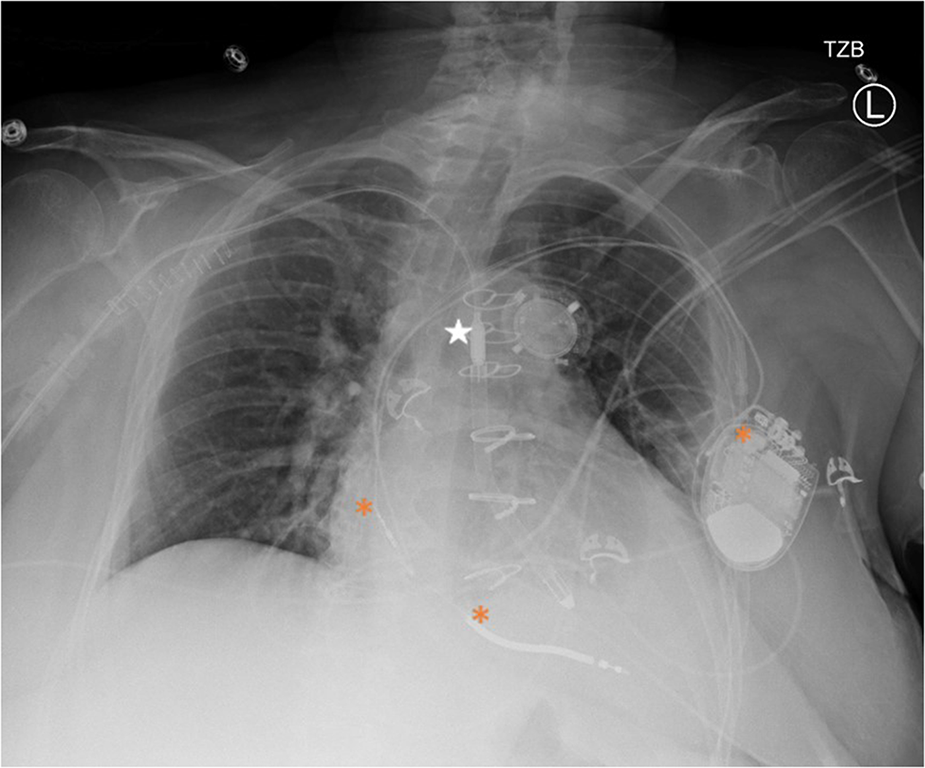

Impella was set to P4 with an estimated flow of 2.4 L/min and remained relatively consistent throughout her hospitalization (Figure 1). Bivalirudin 10.4 mg/hr was initiated anticoagulation.

Figure 1

Portable chest x-ray after impella 5.5 placement. Star = Impella 5.5, * = ICD generator and leads in the right atrium and ventricle.